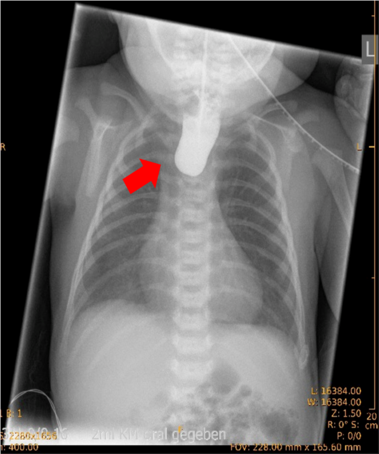

Ösophagusatresie (Speiseröhrenfehlbildung)

Ösophagusatresien brauchen in der langfristigen Nachsorge der Erkrankung ein strukturiertes Netzwerk an Expertinnen und Experten. In der Transition werden Fachärztinnen und Fachärzte der Inneren Medizin von besonderer Bedeutung (Medizin 1), um Aspekte der Nahrungsverträglichkeit, des Schluckens, der Anastomosen- und Refluxbehandlung, aber auch Auffälligkeiten der Lungen und Bronchialwege (Asthma, wiederkehrende Infekte, …) zu behandeln. Wir am Uniklinikum Erlangen bieten Ihnen dieses Netzwerk. Wir arbeiten dabei auch mit Selbsthilfegruppen und internationalen Fachkollegien zusammen.